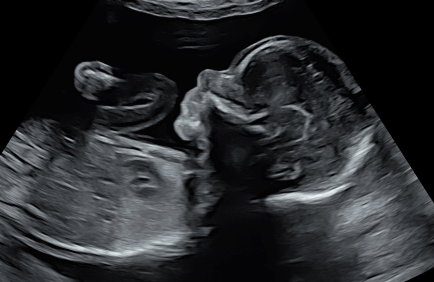

What is 3D/4D Imaging?

1

3D and 4D ultrasound are advanced imaging techniques that allow you to see detailed, three-dimensional images of your baby. 3D imaging produces a still, lifelike image, while 4D adds the element of real-time movement — so you may see your baby yawning, stretching, or even smiling.

Our Expertise

2

At Central West Women’s Imaging, 3D/4D imaging is available for all women as part of our routine obstetric assessment. This is part of our commitment to providing the highest standard of obstetric ultrasound in regional New South Wales. Our sonographers are experienced experts in 3D/4D imaging techniques and use dedicated GE women’s imaging equipment optimised for this purpose.

While we are committed to giving you the best possible experience, we are unable to guarantee a particular 3D/4D image, as this depends on your baby’s position and the amount of fluid around them on the day. Our first priority is always a thorough, high-quality diagnostic ultrasound — we will do all we can within your appointment time to also capture 3D/4D images for you.